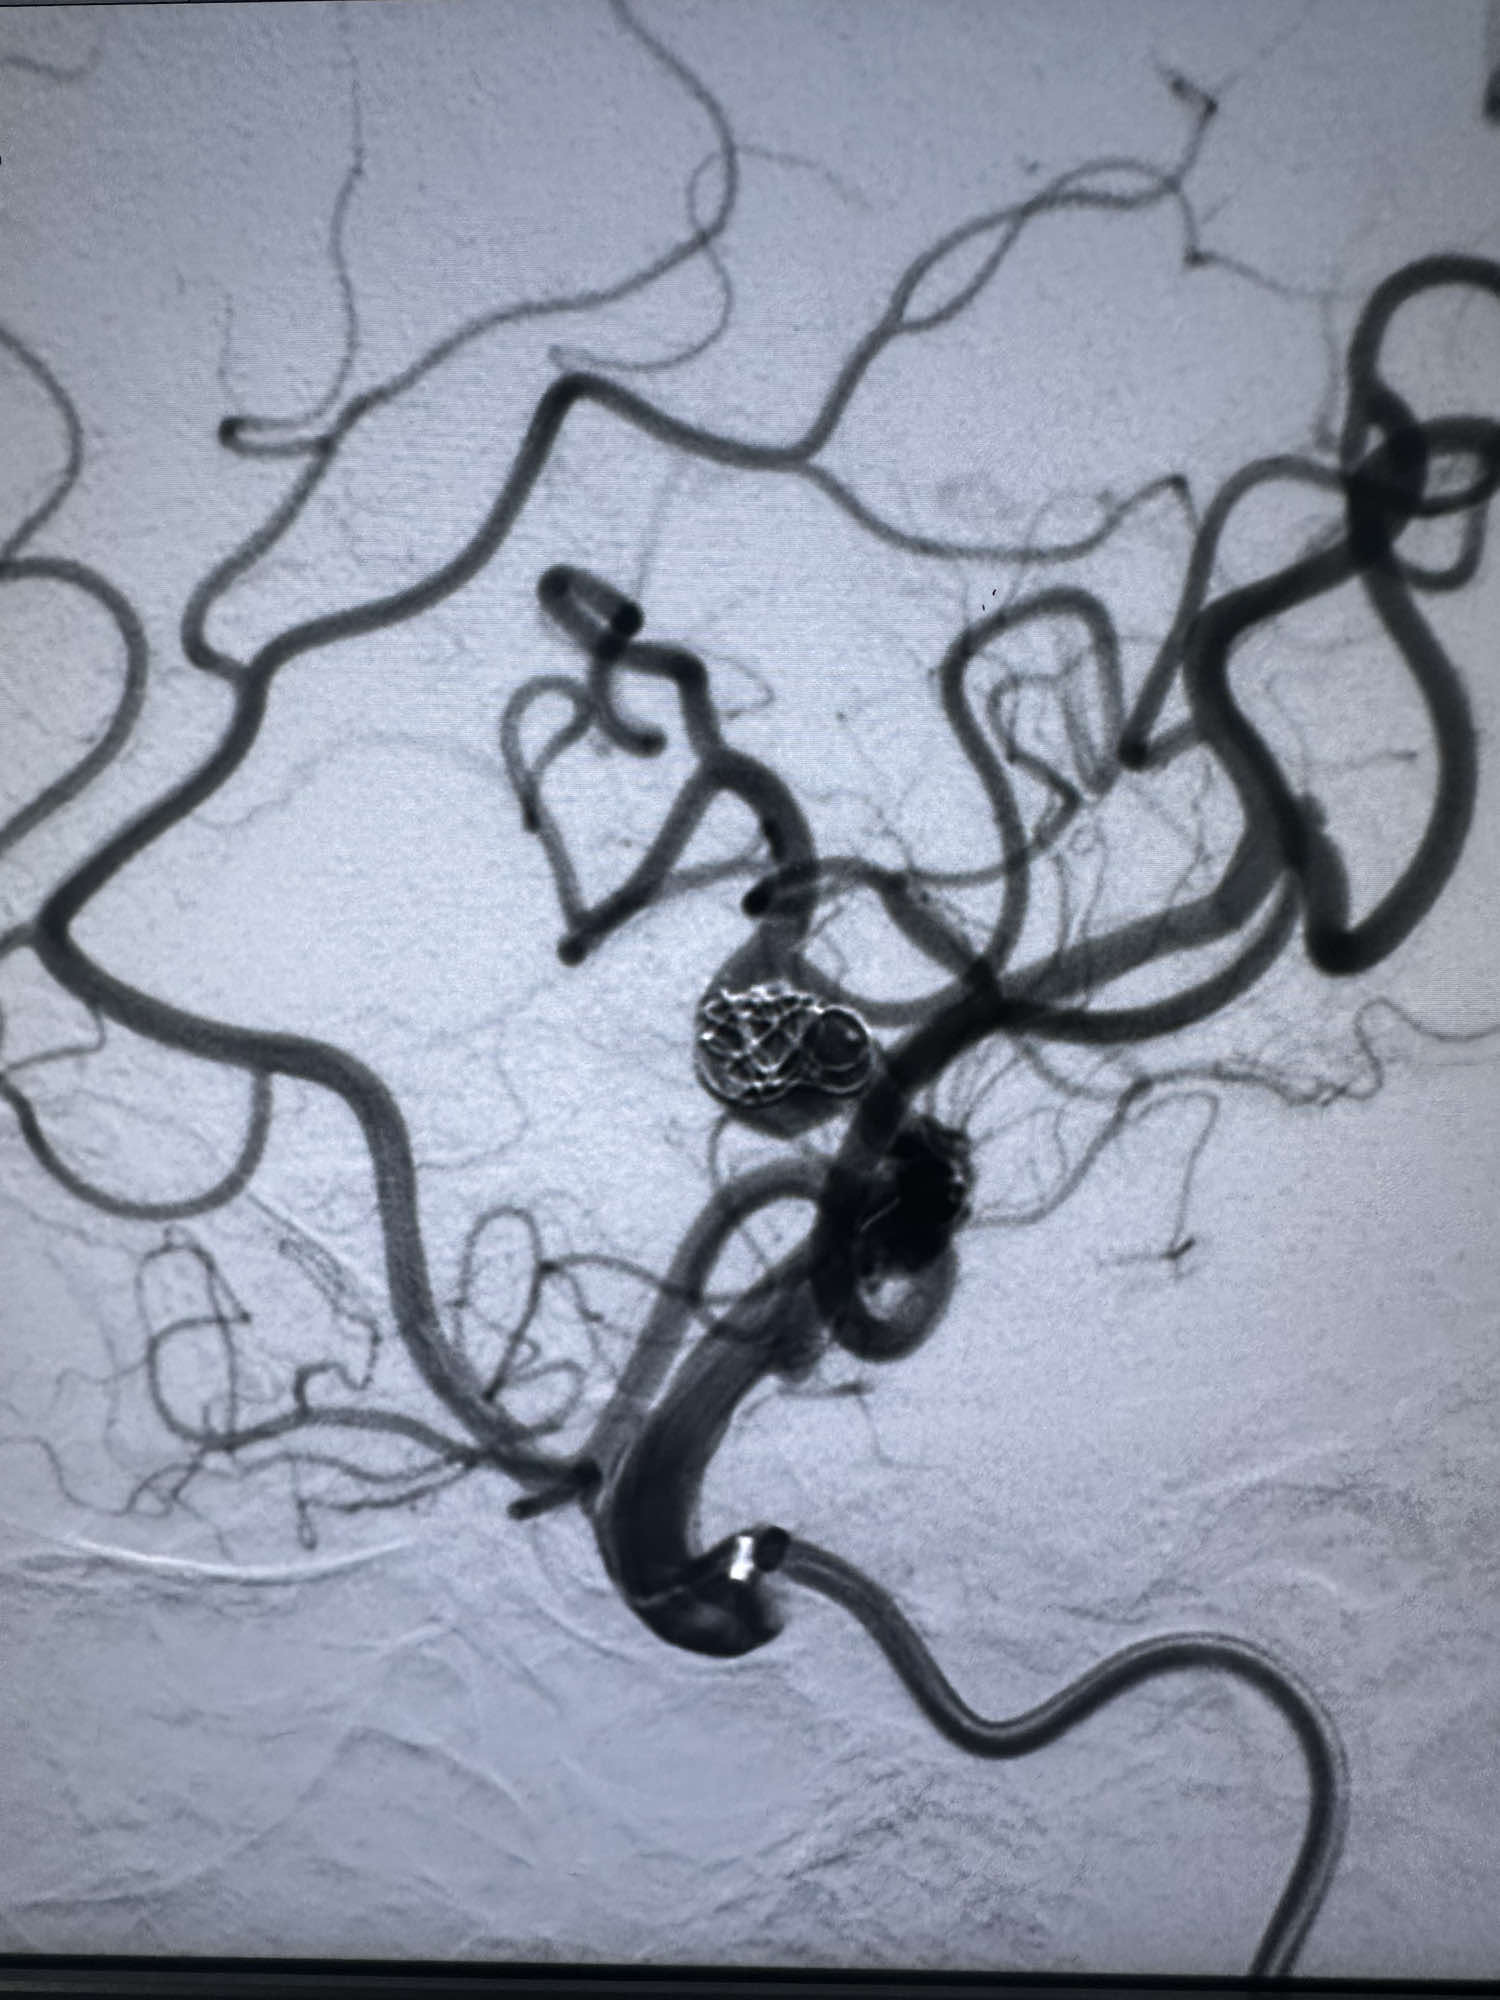

第一枚圈选择6的3D成篮圈,释放支架Atlas 3*15的支架,支架的远端放置在上干

第一枚圈的形态

后续填入多枚史赛克的弹簧圈

最后圈的形态

填塞颞下干的动脉瘤时候,本来想支架导管辅助,支架导管(sl-10)双折进入,可惜最后支撑性太差,微导管没有进入颞下干

直接单纯栓塞处理,第一枚圈选择4*8的3D的弹簧圈

后续填入两枚史赛克的弹簧圈